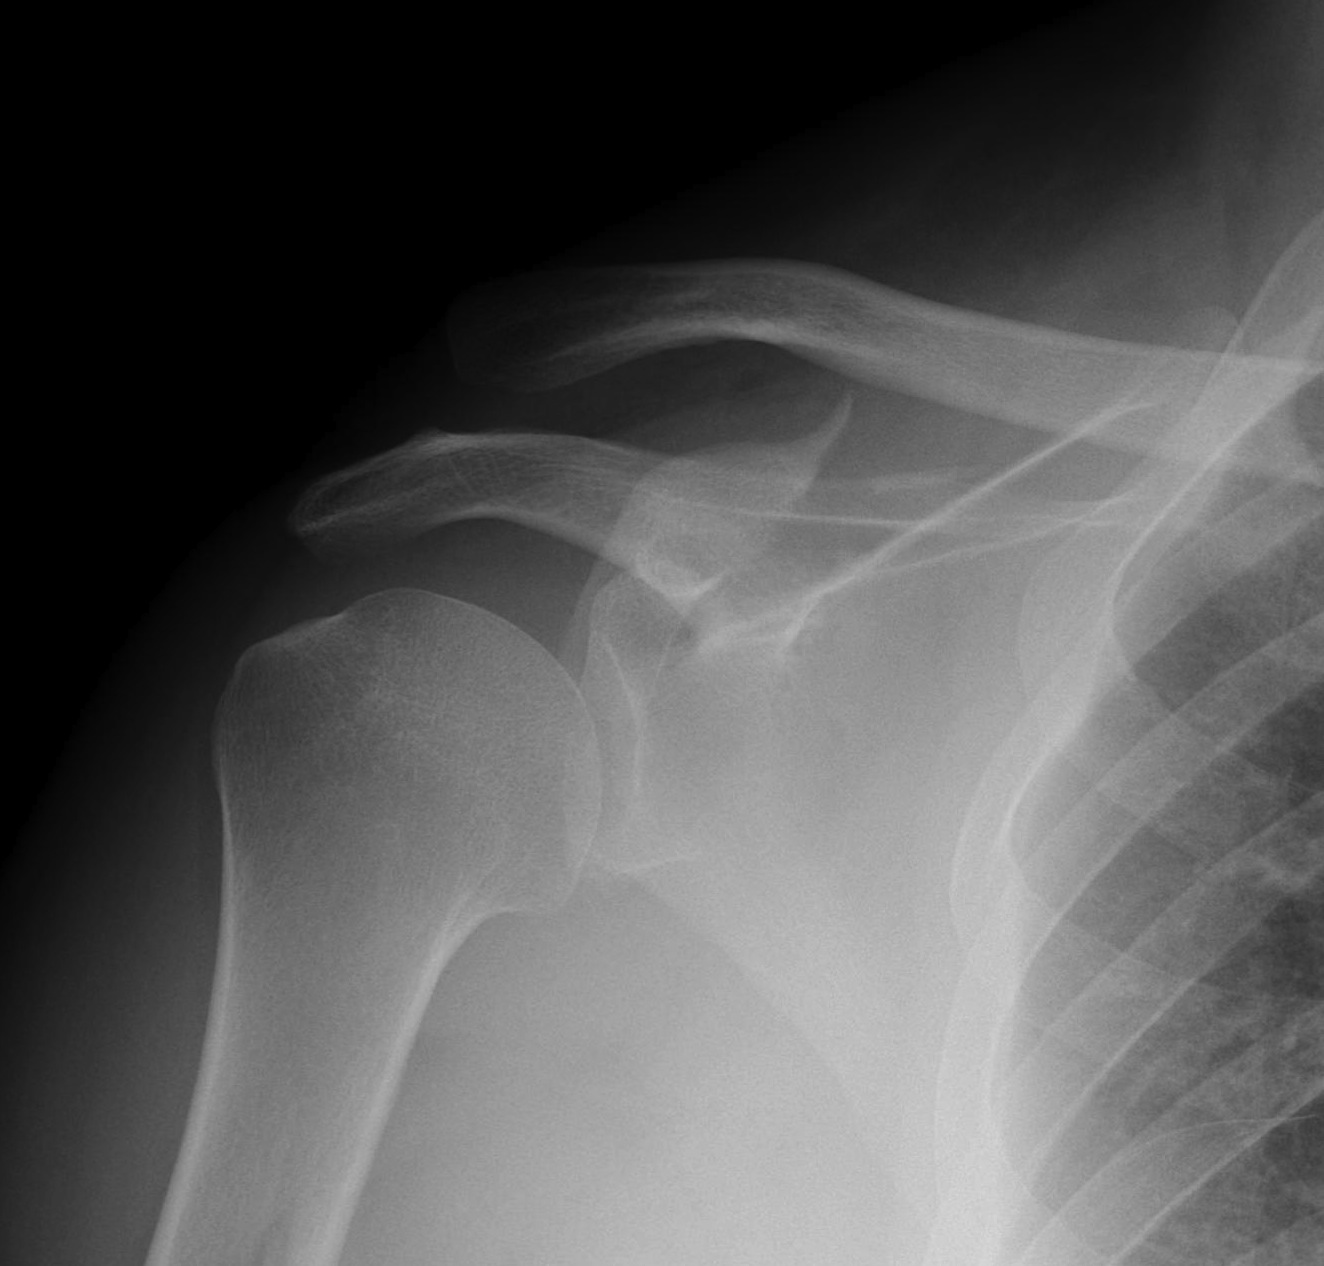

B. Neck

Indications for surgery

- > 450 angulation

- > 10 mm displaced (i.e. medial displacement

Case 1

- > 1 cm medial displacement

- ORIF via posterior / modified Judet approach

Case 2